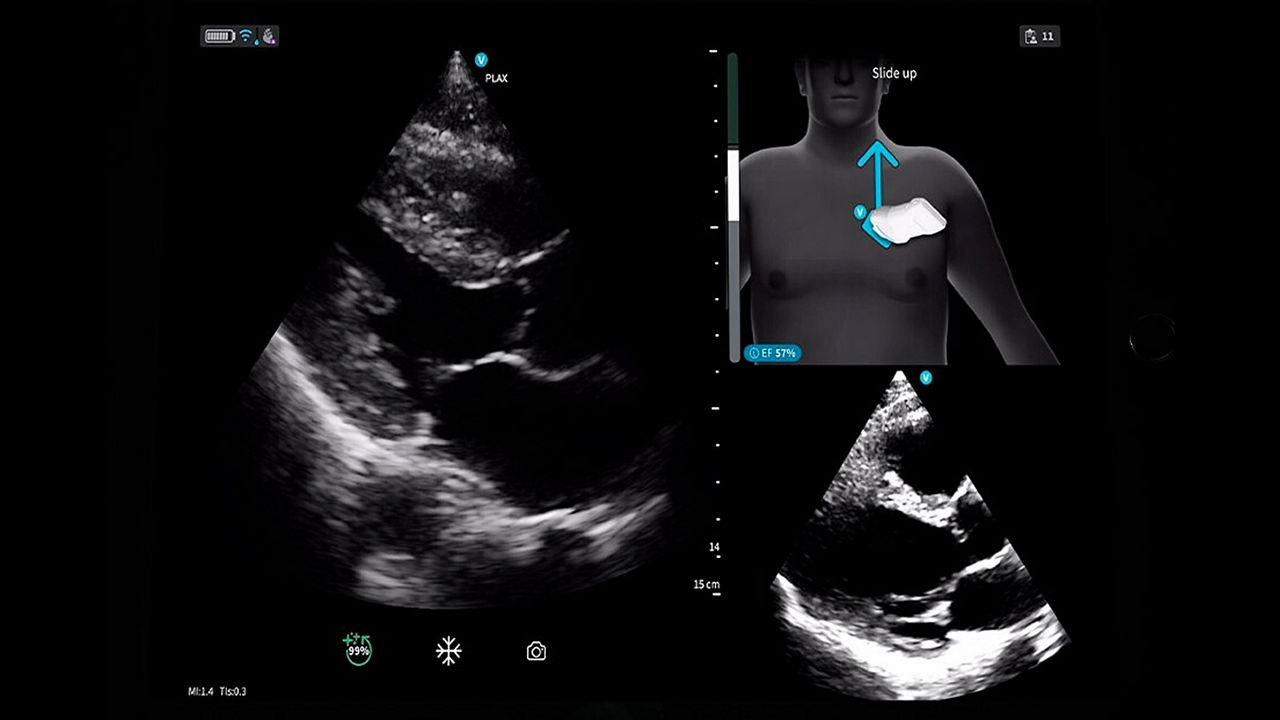

<p>Vscan Air™ SL with Caption AI™</p>

Learn More